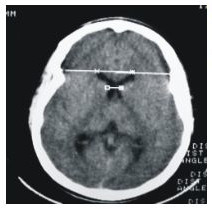

The Brain C/T Scan of 56 Elderly Nigerians made up of 20 cases of clinically diagnosed Dementia (Study Group) and 36 Non-Demented cases that are considered free of significant Cognitive impairment (Control Group), were evaluated. The subjects were selected and categorized based on their performance on the screening tests, which consist of both a screening stage and a Clinical assessment stage. The Study group recorded a significant smaller Brain (142.93+/- 91.6) than the Control group (148.6+/-12.7), and is associated with larger Ventricular sizes. No statistically significant Sex difference was established in both Clinical groups studied. The expected Linear Age relationship with Brain size was found to be less applicable in the Dementia study group, which is attributed to the pathology of the Alzheimer's disease (AD). Cortical Atrophy was the predominant Brain C/T changes found in both Clinical groups studied, but they are more pronounced, though not statistically significant, in the Dementia group. The statistically significant lower MMSE (11.6+/-5) recorded in the Dementia group shows that a significant relationship exist between level of cognitive deterioration and C/T indices of Brain Atrophy.